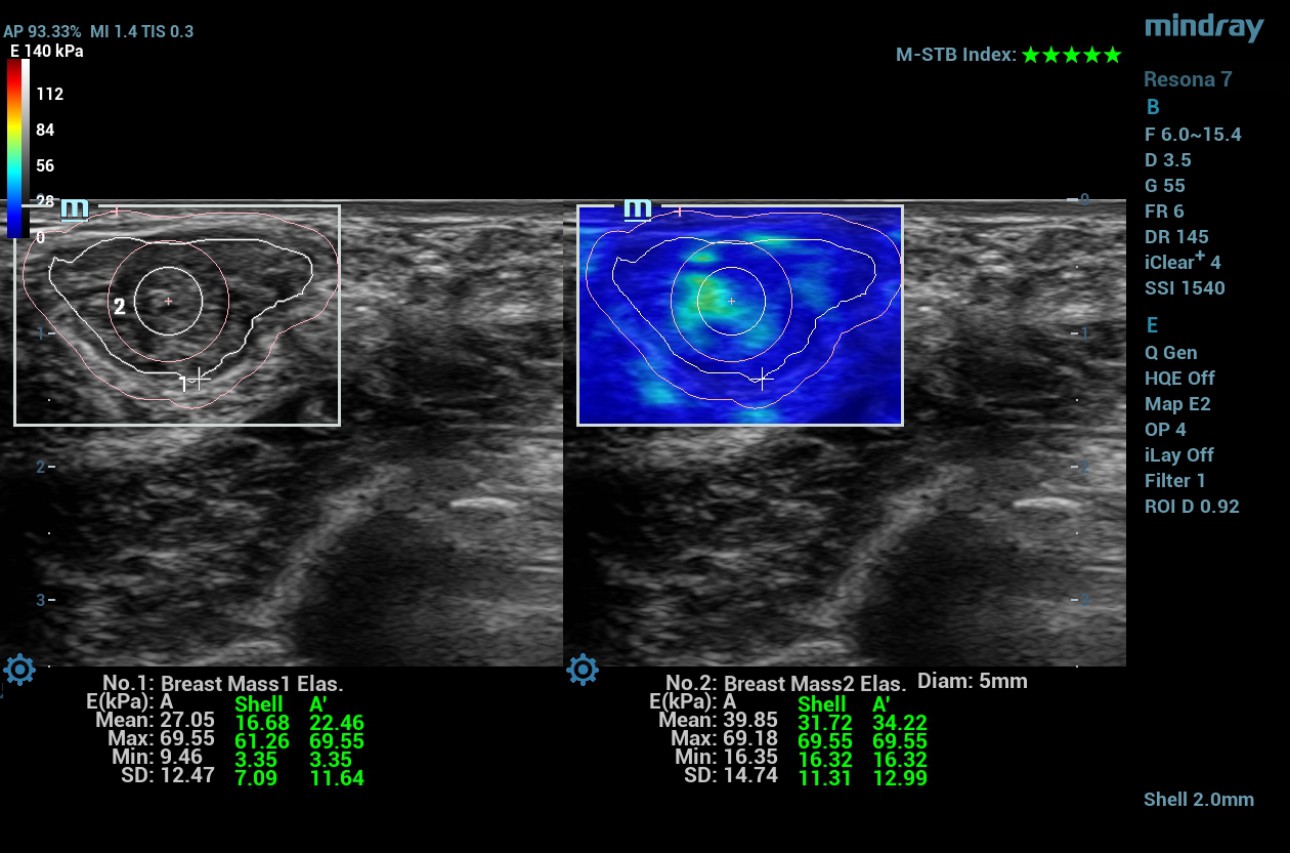

Case 2

21-year female Patient B presented with breast pain in the right breast and was found to have a small lump in the right breast measuring 21x12mm. It was categorized as BIRADS 3 on the ultrasound examination and subjected to shear wave elastography before the biopsy.

SWE findings

The Maximum and mean values in the selected ROI manually along the edge of the lesion are 69.5 kPa and 27 kPa. The maximum value in the 2mm shell around the lesion is 61.2 kPa. The maximum and mean values in the lesion + shell are 69.5kPa and 22.4kPa. Maximum and minimum values in the center of the lesion in a circular ROI measuring 5mm in diameter are 69.18kPa and 39.8kPa.

Malignant tissue is stiffer than benign breast tissue due to the high proliferative index resulting in high cellular density. This principle is utilized in elastography to identify suspicious lesions. The combination of B-mode and SWE increases the specificity in diagnosis from 61% to 79%, and the positive predictive value from 53% to 67% [1]. Few studies have proven that the tissue adjacent to the lesion showed more stiffness than the lesion itself. They have reported that the peripheral tissue of malignant lesions is typically stiffer than that of benign lesions because the former has abnormal stiff collagen fiber, which is related to cancer fibroblasts, as well as infiltration of cancer cells into the surrounding tissue [2]. Mindray Resona 7 system has introduced an option to measure the shell around the specific ROI. In the Resona 7 system, the cut-off value in differentiating benign and malignant was reported as 98.66 kPa in the measurements where a shell of 2 mm in thickness was included [3]. The two cases show that the elastography values were compatible with the histology findings. The measurements taken in the lesionŌĆÖs center were incompatible with patient A's histology findings. It may be due to the center of cancer undergoing necrosis and cystic degeneration. Studies have proven tumor active proliferation can lead to local ischemia, necrosis, and cystic changes affecting the average hardness of tissues [4].